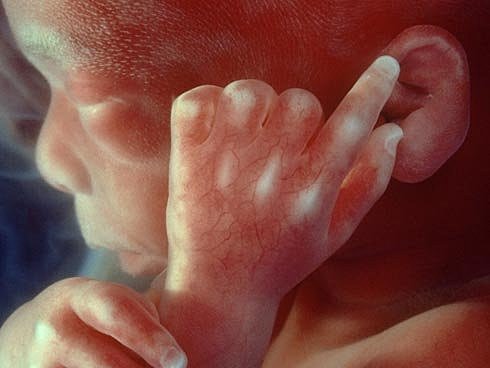

SEMANA18: identifica más sonidos, genitales formados, inicio huellas dactilares.

SEMANA19: extremidades en proporción, crece pelo, orejas y ojos casi en posición final, niñas: ovarios con óvulos, sentido del oído, líquido amniótico (gusto).

SEMANA20: practica sistema respiratorio/digestivo, desarrollo áreas destinadas a sentidos.

SEMANA21: movimiento, posiciones peculiares, siestas.

SEMANA22: órganos vitales, sistema límbico progresa, emociones, siente comunicación y genera respuesta emocional.

SEMANA23: movimientos se perciben, piel rojiza/arrugada, ojos desarrollados, sentidos en desarrollo, conexión a la mamá (ánimo repercute)

SEMANA24: surfactante pulmonar, reconocer y responder a estímulos, maduración órganos, sensaciones del exterior, olores y sabores (líquido amniótico)

SEMANA25: definición pelo, pestañas y abrir/cerrar ojos, vasos sanguíneos pulmones y huesos.

SEMANA26: reacción a la luz (ojos), cuerdas vocales, hipo fetal común.